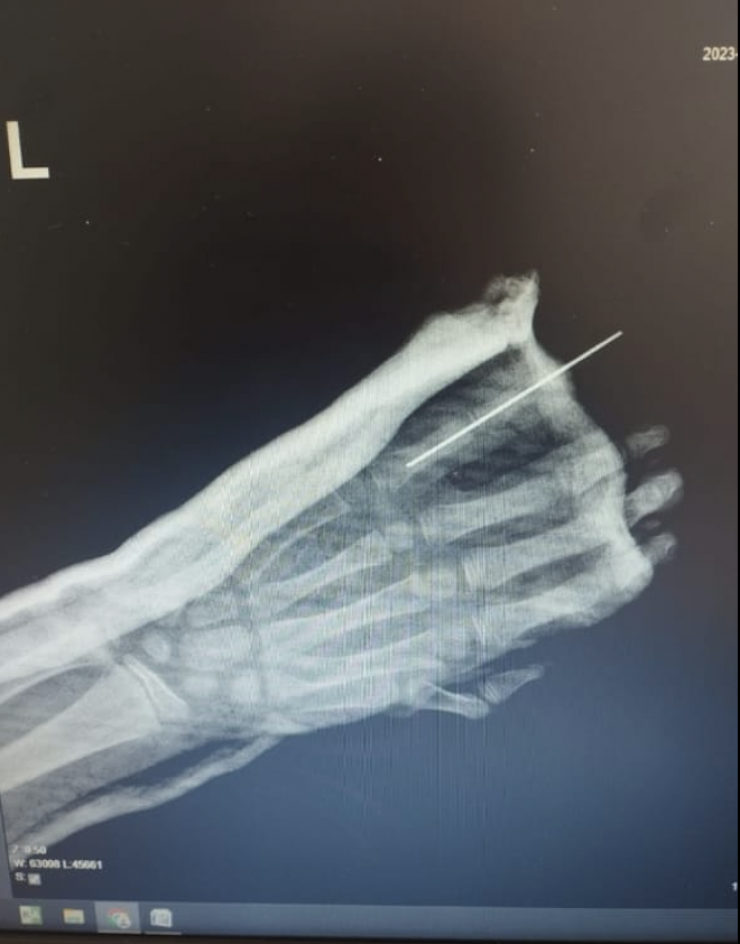

9-летнему мальчику пришили пятый палец руки, отчлененный в результате уличной травмы.

Операция длилась непрерывно около 5 часов. Это очень кропотливая работа. Хирурги под операционным микроскопом сшивали ткани и сосуды, соединяли поврежденные пальцевые артерии, нервные волокна очень малого диаметра. Были восстановлены кость, сухожилия, вены и кровообращение в присоединенном пальце.

"Для проведения такой операции необходима современная микрохирургическая техника: требуется микроскоп, микрохирургический инструментарий и очень тонкий шовный материал, который сложно увидеть невооруженным глазом, все это имеется у нас во 2-й детской больнице. Нам пришлось шить сосуды диаметром 1,2 миллиметра. Без должной подготовки, оборудования, инструментов и расходных материалов проведение таких операций невозможно", - рассказал заведующий отделением травматологии ДГКБ № 2 Ерлан Садырбалин.

Профессионально выполненная реплантация позволила избежать возможных рисков, вернуть подвижность, чувствительность поврежденной части кисти. В течение 8 дней мальчик получал стационарное лечение, палец полностью прижился, рассказали хирурги.